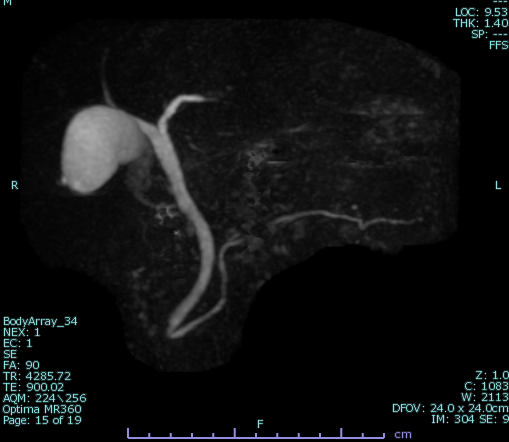

MRCPは、MRI(磁気共鳴画像)装置を使い、胆のう・胆管・膵管といった体内の“管”を詳しく調べる検査です。通常、こうした部分を詳しく調べるには内視鏡を使う必要がありましたが、MRCPは横になっているだけで、体に負担をかけずに詳しい画像を得ることができます。体への負担が少なく、安心して受けていただける検査のひとつです。

MRCPは磁気を利用するため体型やガスの影響を受けにくく、膵臓の異常の早期発見に優れています。